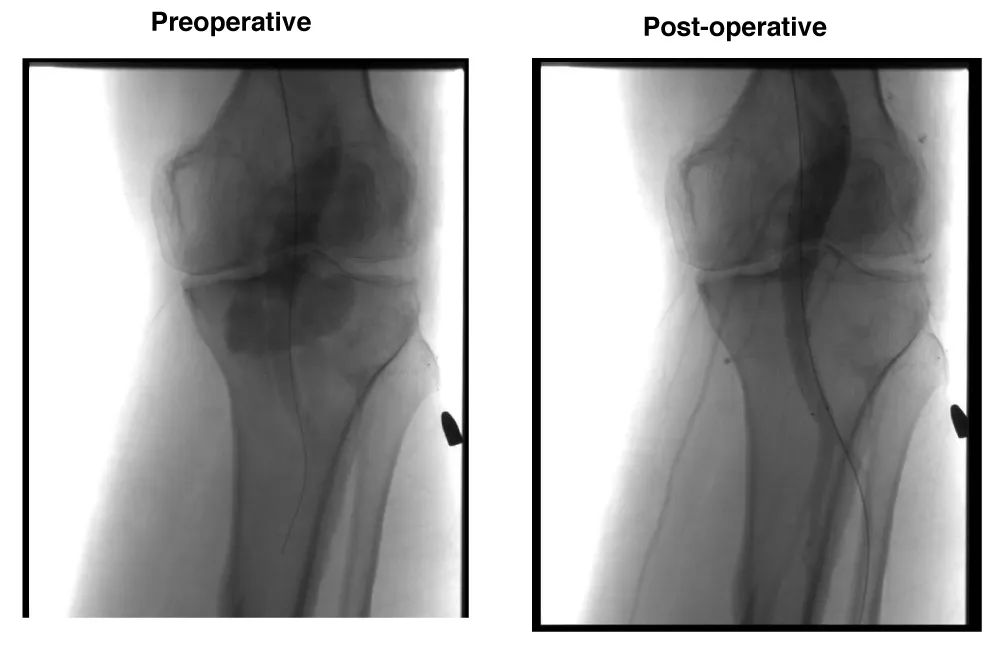

Male patient, 51 years, with arterial hypertension and a history of trauma due to gunshot. The patient evolved with a high-output arteriovenous fistula in the popliteal region causing significant symptoms and 30 mm a popliteal aneurysm. Due to this important symptom, the patient was scheduled to undergo an endovascular procedure with the popliteal implant of endoprosthesis Wrapsody® 12x80 mm at the distal neck, followed by the implant of Wrapsody 14x80 mm and two Wrapsody 16x80 mm at the proximal neck, followed by catheter balloon dilatation. (Figure 2). The patient was discharged from the hospital first day post-operative with Rivaroxaban 20 mg/day and a 6-month follow-up showed endoprosthesis patency and no endoleaks with complete resolution of the previous symptoms.

Figure 2: Endovascular treatment of a 51-year-old male with traumatic arteriovenous fistula and popliteal aneurysm (30 mm): Preoperative angiogram displays fistula formation and aneurysmal dilation. Postoperative image shows complete aneurysm exclusion using four Wrapsody® stents (12×80 mm, 14×80 mm, and two 16×80 mm), with restored vessel continuity and resolution of fistulous flow.